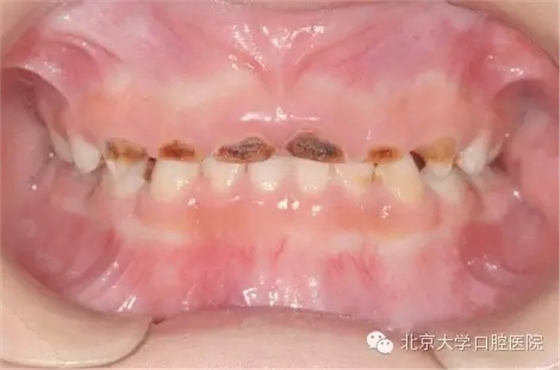

全身麻醉下兒童牙齒治療是怎么回事?

全身麻醉下兒童牙齒治療是一項(xiàng)針對(duì)在口腔醫(yī)學(xué)臨床工作中難于對(duì)牙科恐懼癥患兒、低齡及智障兒童實(shí)施常規(guī)口腔診療的特色技術(shù)項(xiàng)目。從1999年開始,北京大學(xué)口腔醫(yī)院兒童口腔科和麻醉科相互協(xié)作在國內(nèi)率先開展該治療技術(shù)。近二十年來,北大口腔醫(yī)院兒科已建成了設(shè)備先進(jìn)的全麻治療室,累計(jì)完成全麻下牙齒治療患者數(shù)千例,使該技術(shù)成為北大口腔醫(yī)院特色醫(yī)療技術(shù)之一。該治療技術(shù)優(yōu)點(diǎn)是在一次治療中醫(yī)生可以高質(zhì)高效地完成全口所有需進(jìn)行的治療工作,特別適用于配合能力差,治療需要量大的患兒。